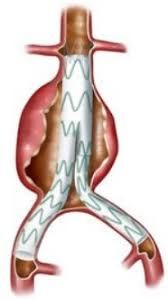

Dirigente Medico di ruolo presso U.O.C. Chirurgia Vascolare ed Endovascolare Ospedale San Giovanni di Dio e Ruggi d’Aragona di Salerno. Pratica attività ambulatoriale, laboratorio di diagnostica ultrasonografica, diagnostica angiografica e attività di sala operatoria (chirurgia open ed endovascolare). L’attività chirurgica tradizionale ed endovascolare comprende il trattamento delle lesioni stenotiche/ostruttive dei tronchi sovraortici (carotidi), lesioni stenotiche/ostruttive delle arterie periferiche e viscerali, degli aneurismi dell’aorta e aneurismi periferici e viscerali (sia in elezione che in urgenza), inoltre l’attività chirurgica comprende il trattamento della patologia venosa (vene varicose/varici) secondo le tecniche chirurgiche classiche (es. stripping) e moderne (laser, radiofrequenza, scleroterapia maggiore), scleroterapia minore di teleangectasie e vene reticolari (estetica vascolare).